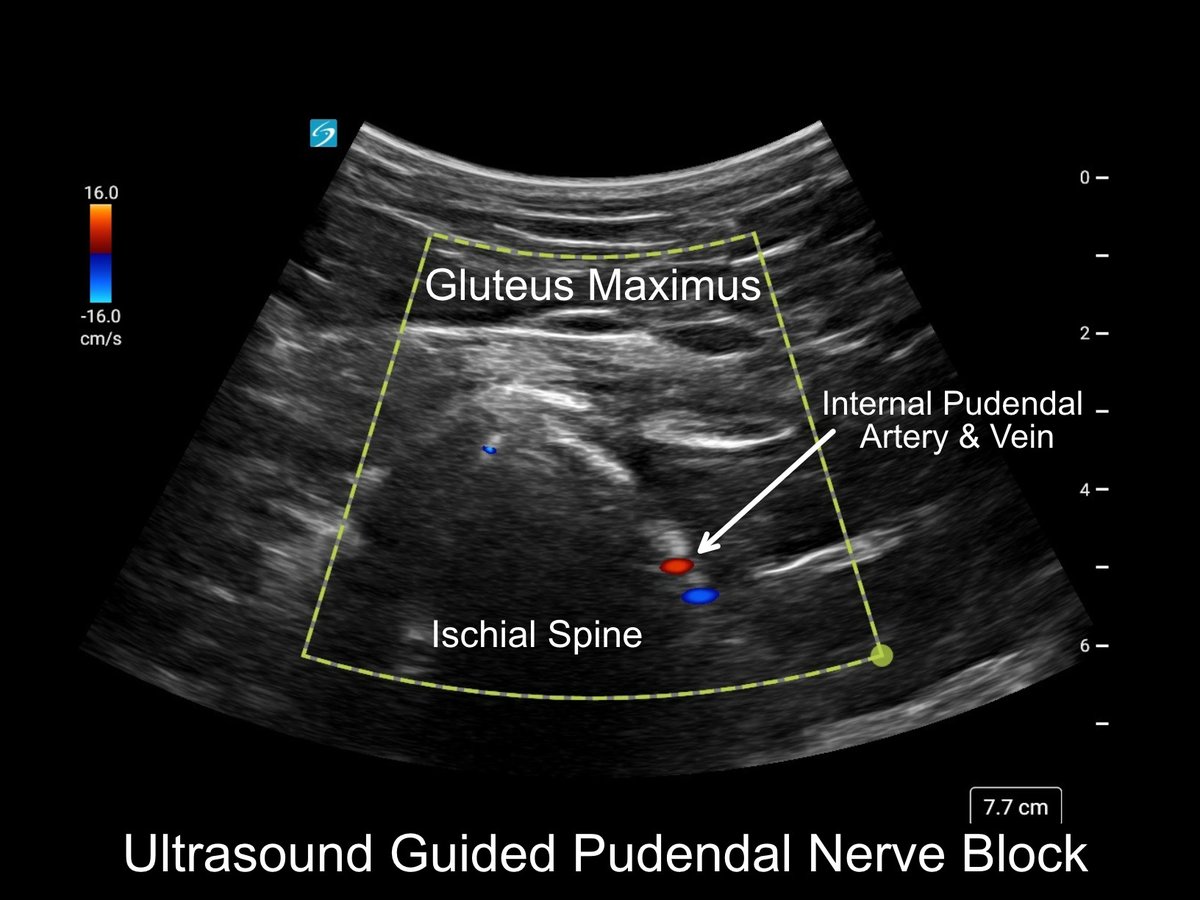

@ASPSP_Pain is the only society that exclusively advocates for non-opioid post surgical pain management by bringing together surgeons and anesthesiologists , empowering them with the tools and education needed to better care for the surgical patient. Join the Us !!